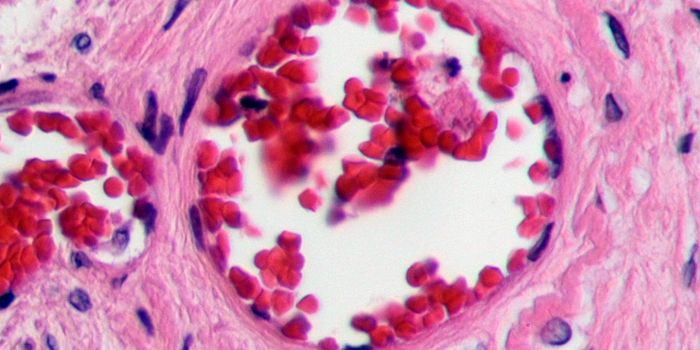

MAY 01, 2018CancerResearchers have developed a microfluidic device that can detect circulating plasma cells in whole blood; therefore, neg ...